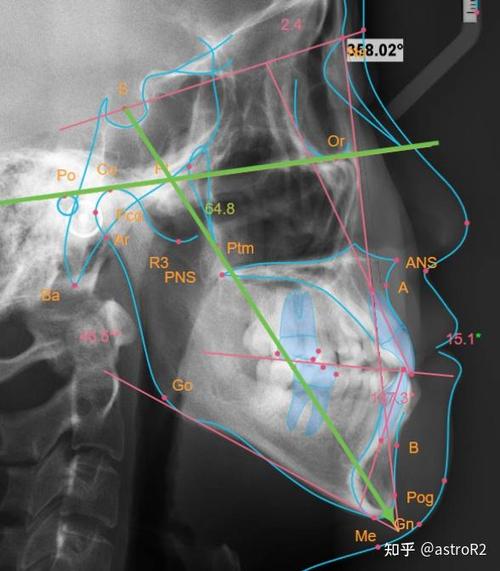

头影测量的基础是头颅定位仪的标准化使用,确保拍摄时患者颅部与X线球管的位置固定,消除因头部倾斜导致的误差,常用标志点包括颅底点(S)、鼻根点(N)、蝶鞍点(Sella)、上齿槽座点(A)、下齿槽座点(B)等,这些标志点的连线构成重要参考平面,如SN平面(由S和N连线构成,代表颅底基准)、FH平面(由眶下缘与耳点连线构成,代表眶耳平面)、MP平面(下颌下缘切线,代表下颌平面),通过测量这些平面间的角度和距离,可量化分析颌骨矢状向(如上下颌骨前后位置关系)、垂直向(如面部高度比例)及水平向(如宽度协调性)的异常。

美国正畸临床中,头影测量指标可分为骨骼、牙齿及软组织三大类,骨骼指标中,SNA角反映上颌骨相对于颅底的位置,正常值约82°±3°,SNA角增大提示上颌前突,减小提示上颌后缩;SNB角反映下颌骨相对于颅底的位置,正常值约80°±3°,SNB角增大提示下颌前突,减小提示下颌后缩;ANB角则综合评估上下颌骨的矢状关系,正常值2°±2°,正值Ⅲ类骨面型,负值Ⅱ类骨面型,垂直向指标如前面高(N-Me)与后面高(S-Go)的比值(正常值约62%~65%),可判断面部垂直比例是否协调,过大或过小可能导致“长面型”或“短面型”畸形,牙齿指标包括上中切牙凸距(U1-APg,正常值2~4mm)、下中切牙斜度(L1-MP,正常值95°±5°),用于评估牙齿唇倾度及与基骨的关系,避免治疗中牙根吸收或唇侧骨开窗,软组织指标如鼻唇角(鼻小柱与上唇交角,正常值90°~100°)、软组织颏前点(Pos-Pog)距离,直接关联患者面部美观,是制定正畸-正颌联合治疗的重要参考。